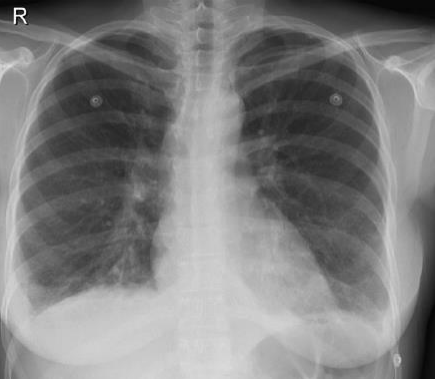

De acordo com o RX de tórax da paciente, apesar da ausculta pulmonar limpa, ela apresenta

Leia o caso clínico que segue para responder às questões de 32 a 36.

Um jovem médico resolve fazer, pela primeira vez, um plantão noturno na emergência. Na madrugada, uma senhora de 75 anos, hipertensa e diabética dá entrada com queixa de dispneia e taquicardia. Ao exame clínico, observou-se FC = 122 bpm, PA = 140x90mmHg, ausculta pulmonar limpa, discreto edema de membros inferiores e Sat. O2 95%. Trouxe um ecocardiograma recente que mostrou diâmetro ventricular esquerdo normal, aumento discreto de átrio esquerdo, hipertensão pulmonar discreta e FEVE = 62%.

O médico solicitou os seguintes exames a seguir: